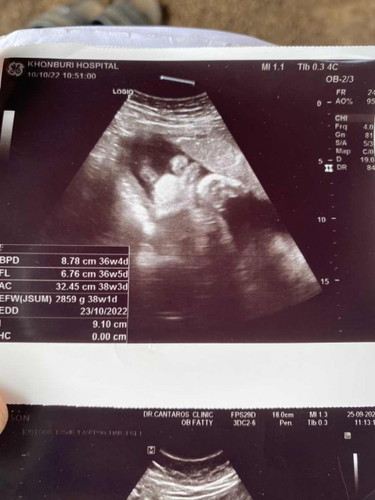

น้ำหนักลูกในครรภ์

ไปซาวมาวันนี้35w6dน้ำหนัก2859gถือว่าเยอะไปไหมค่า🥰